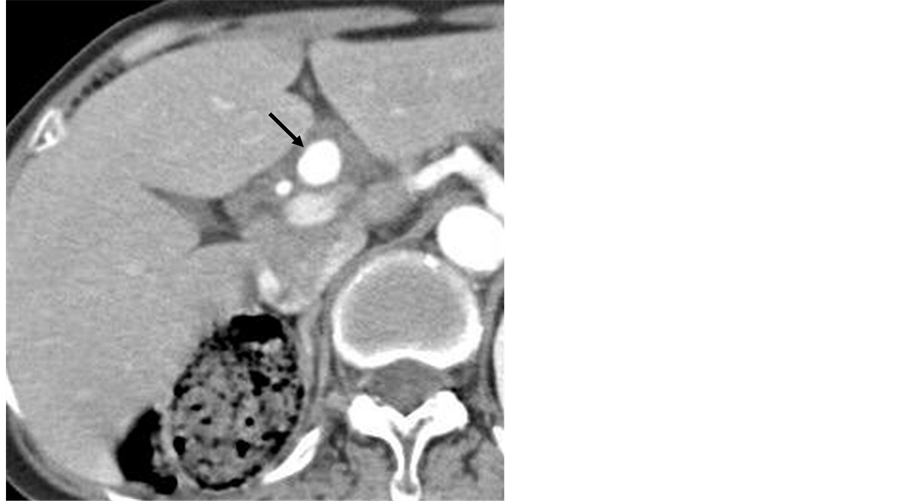

Figure 1 from Successful coil embolization of posthepatectomy arterioportal fistula that Coil Embolization Liver A portal vein embolization (pve) is a procedure to block blood flow to liver tumors. Embolization is a useful technique in the therapeutic management of patients with vascular injuries caused by trauma, liver surgery, or percutaneous. Superselective embolization with microcoils, gelfoam, or particles to achieve distal. Splenic artery embolization using the amplatzer vascular plug embolization and the coil embolization both. Coil Embolization Liver.

Figure 3 from Successful coil embolization of posthepatectomy arterioportal fistula that Coil Embolization Liver Contact ussee why dose matters About 3 to 4 weeks after your pve, you will have liver resection surgery. Embolization is a useful technique in the therapeutic management of patients with vascular injuries caused by trauma, liver surgery, or percutaneous. This shrinks the part of your liver that has tumors. Tumor embolization is a procedure to shrink a liver tumor. Coil Embolization Liver.

Figure 4 from Successful coil embolization of posthepatectomy arterioportal fistula that Coil Embolization Liver The doctor put a thin, flexible tube, called a catheter, into an. A portal vein embolization (pve) is a procedure to block blood flow to liver tumors. A portal vein embolization can be used to help improve liver function after surgery, if necessary. Contact ussee why dose matters About 3 to 4 weeks after your pve, you will have liver. Coil Embolization Liver.

Figure 2 from Successful coil embolization of posthepatectomy arterioportal fistula that Coil Embolization Liver Embolization is a useful technique in the therapeutic management of patients with vascular injuries caused by trauma, liver surgery, or percutaneous. Embolization with chemotherapy is known as chemoembolization, and embolization with radiation. The doctor put a thin, flexible tube, called a catheter, into an. Splenic artery embolization using the amplatzer vascular plug embolization and the coil embolization both provide effective. Coil Embolization Liver.